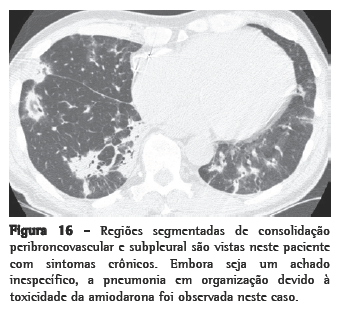

Padrão 3. Opacidade pulmonar aumentada

Opacidade pulmonar aumentada pode ser descrita como opacidade em vidro fosco ou consolidação. A opacidade em vidro fosco (Figura 15) é uma opacidade pulmonar aumentada que não obscurece os vasos associados e representa anormalidades abaixo da resolução da TCAR. A consolidação (Figura 16) é uma opacidade pulmonar aumentada na qual os vasos são obscurecidos e representa uma doença confluente. Estes achados são muito inespecíficos e podem refletir doenças que são primariamente alveolares, intersticiais ou mistas. O diagnóstico diferencial entre opacidade em vidro fosco e consolidação muitas vezes é sobreposto e é predominantemente baseado pela duração dos sintomas: agudo ou crônico (Quadro 8). A distribuição dos achados (focal, segmentado ou difuso/simétrico) pode ser útil no estreitamento do diagnóstico diferencial (Quadro 9).

Formas crônicas de pneumonia em organização

Formas indolentes (smoldering) e crônicas de PO não-infecciosa podem produzir achados clínicos de dispnéia progressiva, febre baixa, sintomas constitucionais e consolidações pulmonares que não respondem ao tratamento padrão para pneumonia infecciosa. Muitas condições podem resultar em PO. Em um estudo conduzido na cidade de São Paulo, Brasil, envolvendo 95 pacientes, a PO era idiopática em um terço dos casos e secundária a uma causa identificável nos casos remanescentes.(90) As causas mais comuns eram: drogas (especialmente amiodarona e MTX), exposição ambiental (tal como as observadas em PH), aspiração crônica e DTC. Consolidações, centrais ou periféricas, foram encontradas em 64% dos casos; opacidade em vidro fosco, em 53%; e nódulos, em 26%. A biópsia transbrônquica foi diagnóstica em 58% dos casos.

Na pneumonia em organização criptogênica (POC), padrões típicos na TC consistem em consolidações parenquimatosas periféricas com broncogramas aéreos e opacidades em vidro fosco com associação variada.

As consolidações na POC sugerem o diagnóstico quando distribuições subpleurais e peribroncovasculares ocorrem ­conjuntamente ou quando as opacidades são migratórias.(91) O sinal em forma de atol ou halo reverso (uma opacidade em vidro fosco central cercada por um aro ou anel de consolidação) é encontrado na PO, mas também pode ser visualizado em outras condições, como PEC e paracoccidioidomicose.(92,93) Em um estudo, um padrão perilobular de anormalidades (opacidades curvilineares que tem maior espessura e, mais importante, menor definição do que aquelas encontradas em septos interlobulares espessados, e com uma aparência em forma de arcada ou poligonal) foi observado em mais da metade dos pacientes.(94)

O diagnóstico de PO é baseado na combinação dos achados clínicos, histológicos e de imagem.(95) Em casos de DTC, casos de exposição a drogas ou a antígenos ambientais, assim como em casos de aspiração, áreas localizadas de PO podem ser um achado patológico secundário.

Portanto, um diagnóstico de PO deve ser feito somente na presença de achados típicos na TCAR, ausência de achados indicativos de fibrose na TCAR e uma boa resposta a corticosteróides. Se estes critérios não forem atingidos, a biópsia pulmonar cirúrgica deve ser realizada.